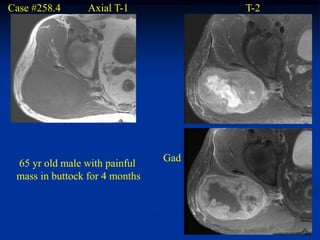

Case #258.4      Axial T-1            T-2

Gad

65 yr old male with painful

mass in buttock for 4 months

Cor T-1   T-2

Sag T-2   Gad

Case #258.4 Axial T-1 T-2 Gad 65 yr old male with painful mass in buttock for 4 months

• 131.

Cor T-1 T-2 Gad